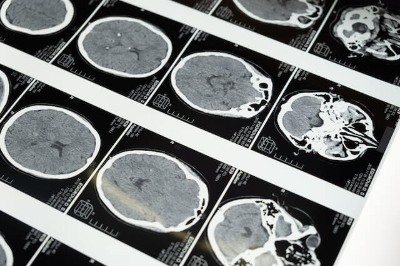

뇌졸중은 뇌혈관 질환으로 뇌에 혈액을 공급하는 혈관이 막히는 뇌경색이나 혈관이 터지는 뇌출혈 모두를 일컬어 뇌졸중이라 하며 가장 중요한 기관인 뇌에 손상이 오고, 그에 따른 신체장애가 나타납니다.한번 손상된 뇌 조직은 되살릴 수 없어 영구적인 신체장애를 유발하므로 뇌졸중 전조증상 파악 및 응급처치가 무엇보다 중요합니다.

3. 응급치료가 중요한 뇌졸중

(1) 뇌경색은 증상 발생 후 적어도 3시간 이내에 적절한 치료(정맥 내( 혈전용해제 투입이나 방사선 직접 중재시술을 통한 동맥 내 혈전 용해술)를) 받아야 뇌 손상으로 인한 후유증과 장애를 최소한으로 줄일 수 있습니다. ☎119

(2) 뇌출혈 또한 가능한 빠른 시간 내에 출혈의 원인을 진단하고 적절한 치료를 받아야 뇌손상으로 인한 후유증과 장애를 최소한으로 줄일 수 있습니다.

(3) 고혈압성 뇌출혈인 경우 출혈량이 적으면 흡수될 때까지 약물치료 등 내과적 치료를 하며, 출혈량이 많으면 전신 마취하에 응급 혈종제거 수술을 시행합니다.